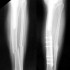

Le diagnostic est radiologie :

Il montre:

- le siège de la fracture

- le trait de la fracture qui peut être unique , complexe multi fragments, spiroïde et toucher plusieurs os ou segments

- le type déplacement de la fracture et sa localisation anatomique